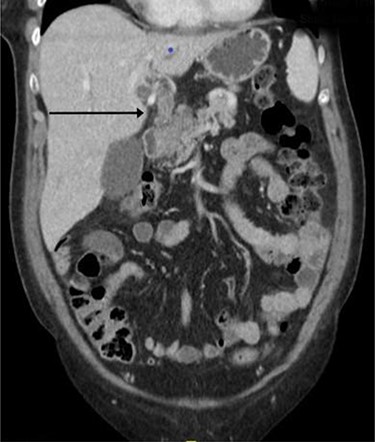

Computerized tomography demonstrated an enhancing soft tissue thickening in the gastric pylorus with soft tissue extension into the left lobe of the liver, invasion of the left intrahepatic bile ducts with obstruction and dilatation of the left sided intra- and extrahepatic biliary tract (Fig. 1). Oesophagogastroduodenoscopy (OGD) showed a pre-pyloric fistula (Fig. 2).

Computed tomography imaging showing continuous tubular structure extending from the left hepatic lobe to the stomach.